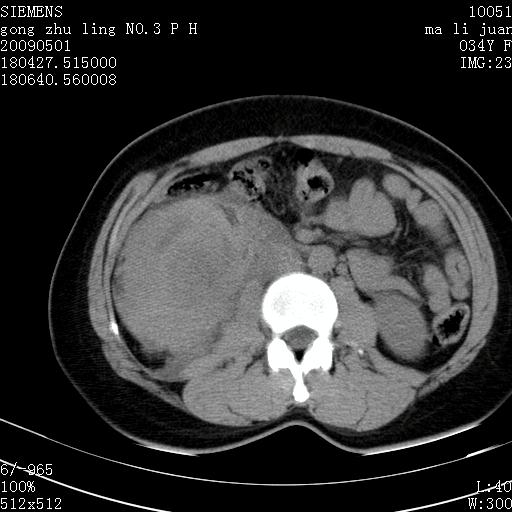

标题: CT19733:右肾碎裂

青年女性,骑摩托车摔伤。

右肾碎裂伤,包膜下血肿。

术中仅见右肾碎裂,肾蒂血管未见断裂。

支持 右肾破裂伴肾包膜下及肾周血肿。

右肾破裂并右侧腹膜后间隙出血。

右肾破裂伴肾包膜下及肾周血肿。